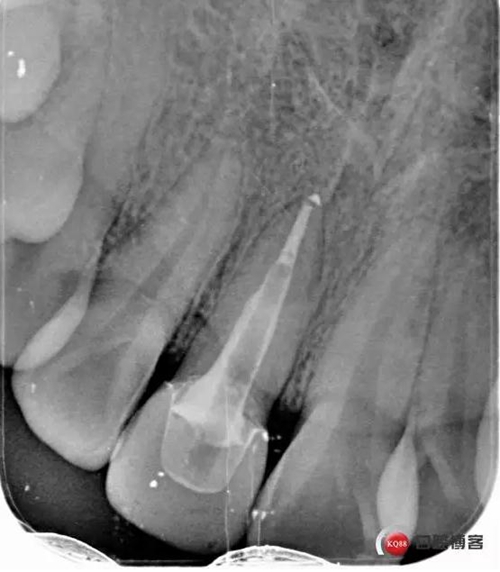

看起來有點頭痛哈,拍片檢查

牙根長度比較號,根充完善。這張片子也可以看出,為什么上次脫落了,樁的深度不夠,而且明顯樁根樁道不匹配,打的樁都沒有到位。

術(shù)后牙片可以看出樁的長度有明顯增加。到達(dá)預(yù)備長度。術(shù)后齦緣高度與鄰牙一致